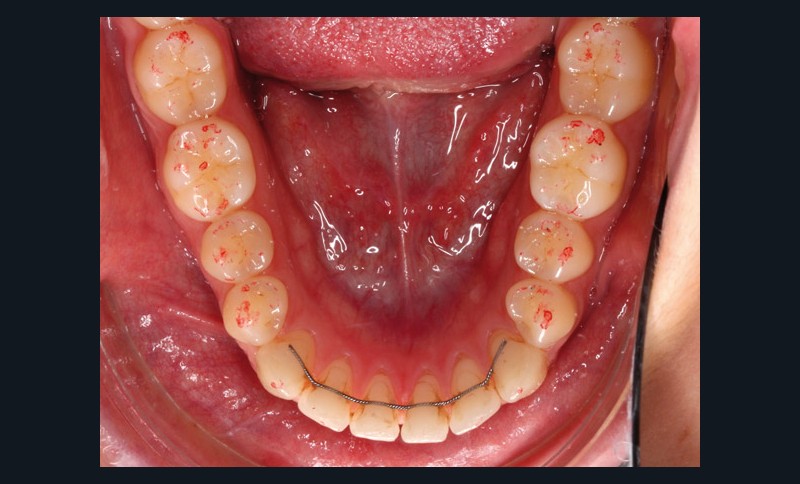

Ces différents aspects dépendent non seulement de la qualité et de l’épaisseur du papier, de son support, de la composition de l’encre, de l’imprégnation salivaire, mais aussi de la force de morsure [3-8]. En fonction du nombre de morsures et de la manière dont le patient serre sur le papier à articuler, la couleur, la taille et la forme des marques varient (fig. 1).

De plus, son utilisation répétée réduit significativement la précision et la sensibilité [4]. Même lorsque ces papiers sont employés dans des conditions idéales, les marques ne sont pas reproductibles [2-5, 9, 10] et le papier à articuler est souvent sujet à des perforations ou des déchirures lors des mouvements de fermeture en intercuspidie [9]. D’autre part, sur un champ humide, l’encre peut diffuser, ou le papier peut se plier, par exemple par retour du papier occlusal…